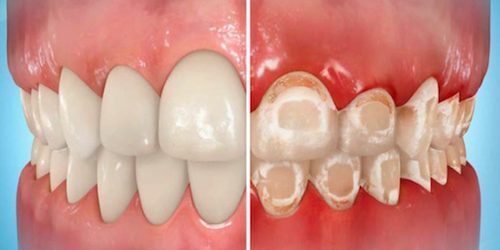

1. 치아탈회

치이표면이 하얀색으로 부식되는 것을 말합니다.

당분이나 산도가 높은 음식물을 과도하게 섭취하거나

칫솔질을 게을리하면 누구에게나 생길 수 있는 증상이기도 합니다.

교정장치 장착 후 양치질이 제대로 되지 않으면 치아 탈회의 가능성이 높아지는데,

한번 탈회된 치아는 다시 회복되기 어렵기 때문에

정도가 심한 경우 충치로 전이되지 않도록 별도의 치료가 이뤄져야 합니다.

초기탈회는 불소도포나 나노 하이드록시아파타이트등의

치아재광화촉진재로 치료할 수 있습니다.

한 번의 치료로 가능한 것은 아니며

탈회된 부위에 부족한 미네랄을 꾸준히 공급해 주어야 합니다.

탈회의 원인이 된 어떤 습관을 개선하는 것도 탈회치료에 매우 중요한 부분입니다.

초기 에나멜 탈회를 치료 하지 않고 방치하면

덴틴으로 침투하므로 적극적인 관리와 치료가 필요합니다.

만약 에나멜 탈회가 덴틴까지 침투하면

레진치료등의 치과보철치료, 라미네이트 등을 시행할 수 있습니다.

치아미백도 시행할 수 있으나 탈회를 치료하는 방법이 아니라

탈회는 감추는 방법이며 도리어 에나멜을 더 손상시킬 수 도 있습니다.